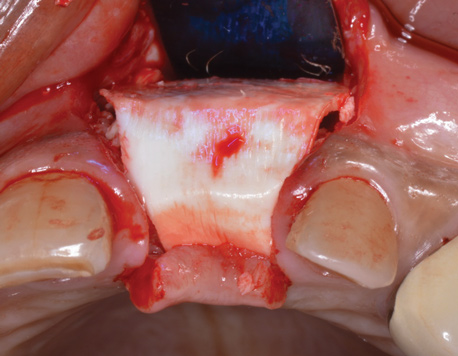

(6.) A 3.6-mm diameter implant was removed with a 4.0-mm diameter trephine drill. The apical portion of the implant was luxated carefully to preserve as much bone as possible.

Figure 6